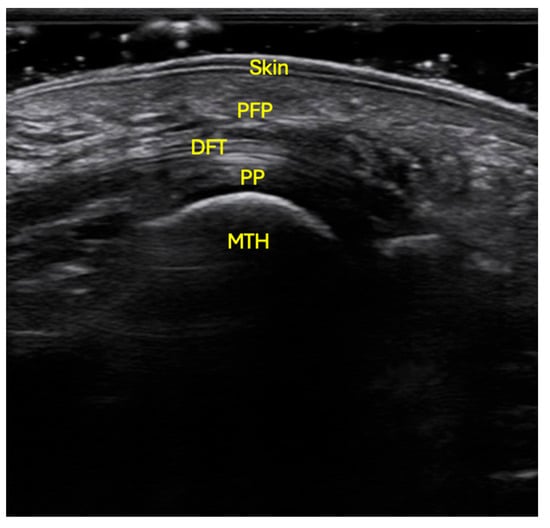

Ultrasound examinations were conducted using a VINNO E35 system (Vinno Technology, Suzhou, China) equipped with a linear transducer model X6-16L, operating at a sampling frequency of 7.3–18 MHz. Participants were positioned prone on the examination table, with the ankle joint in a neutral position and the knee flexed at 90° [16,17]. The skin was cleansed with alcohol to optimize ultrasound penetration. Conductive gel was applied to both the transducer and the plantar surface of the forefoot. The probe was placed longitudinally, aligned with the axis of each metatarsal, without exerting pressure, to obtain a sagittal image free of soft-tissue distortion (Figure 1).

Ultrasonographic localization of the PFP at the level of the 2nd to 5th metatarsal heads. The probe was situated in longitudinal orientation, with no pressure, following the axis of the metatarsal, with the patient in prone position, flexed knee and neutral position of the ankle. Skin; PFP: plantar fat pad; DFT: digital flexor tendons; PP: plantar plate; MTH: metatarsal head.